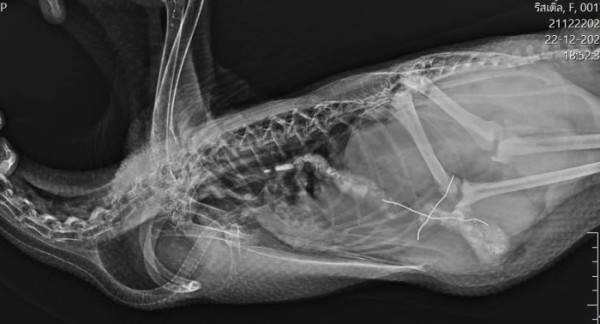

醫院的 X 光顯示,電線卡在小鵝的身體內,必須透過手術才能取出。在麻醉後,醫生為牠剃掉腹部的毛髮並進行手術。術後,小女鵝一臉無辜地攤平在手術床上,兩隻小腳直挺挺地擺著,鵝爸爸則關切地探頭查看,宛如在叮嚀:「下次別再把什麼東西都放進嘴巴裡!」